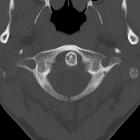

Bogenspalt am

hinteren Atlasbogen in der Computertomographie axial. Zufallsbefund ohne Klinik.